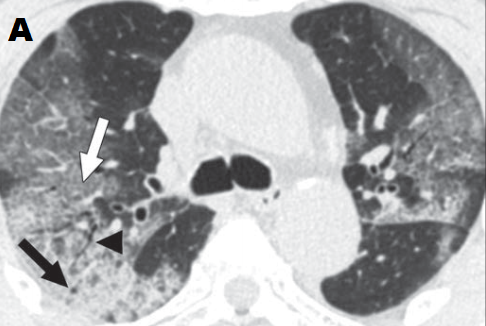

+ Hầu hết các báo cáo cho thấy thương tổn thể hiện bởi hình ảnh đám mờ với các hình thái: từ dạng kính đục đơn thuần (hình 1a)-loại này là nổi trội trong giai đoạn sớm, đến đám mờ dạng kính đục có biểu hiện dày vách liên tiểu thùy, vách trong tiểu thùy, dày dạng lưới (hình 1b), đến đám mờ dạng kính đục kèm đặc phổi từng phần (hình 2A); đám mờ dạng đặc phổi đơn thuần (hình 1c). Đám mờ thường có hình dạng hình học; có một số trường hợp thì các đám mờ dạng kính đục hay đám mờ đặc phổi lại có dạng hình tròn hoặc có biểu hiện dấu halo đảo ngược (dấu hiệu để chỉ thương tổn gồm viền đặc phổi dày tối thiểu 2 mm bao quanh vùng kính mờ ở trung tâm). Một kiểu thương tổn khác là dải mờ gặp với tần suất ít hơn (bảng 1).

+ Ngoài ra còn có một các dấu hiệu khác như: lớn ra của cấu trúc mạch máu bên trong đám mờ thương tổn (hình 2B), dày vách liên tiểu thùy và trong tiểu thùy tạo nên hình ảnh lát đá không đều (hình 1b, 2A), hình cây phế quản khí (hình 2A), dấu halo đảo ngược.